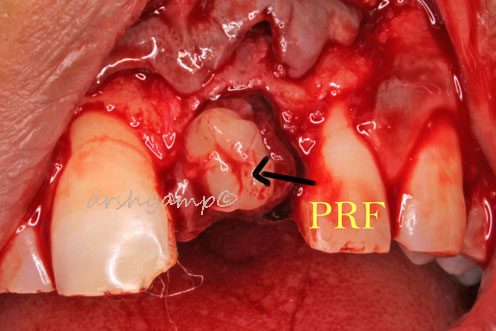

Cyst Enucleation